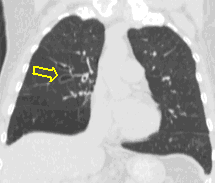

17a, b: Apical TB. HRCT, coronal reconstruction

Right apex, segment 1: reticular pattern and mosaic-like ground glass opacity (similarly mind changes in b. 6th segment, too). Extensive TB-specific lesions in apical dominance.